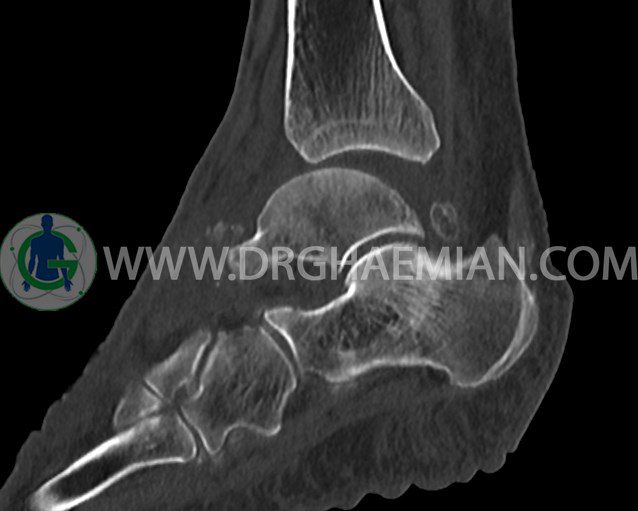

سی تی اسکن مچ پا تصاویری عرضی از مچ پا ایجاد می کند. این روش تصویربرداری از اشعه ایکس برای ایجاد تصاویر استفاده می کند. در این کیس آرتریت مچ پا به همراه سلولیت و تورم نسج نرم در اطراف مچ پا مشاهده می شود.

سي تي اسکن مچ پاي چپ ( مولتي ديدکتور 16 با مقاطع ظريف و بازسازي هاي ساژيتال و کرونال و 3D):

=تورم نسج نرمي در اطراف مچ پاي چپ با شدت بيشتر در اطراف قوزک خارجي

– کانون هاي کلسيفيه در نسج نرم اطراف ديستال ساق ، مچ پاي چپ و در مفصل tibiotalocalcaneous و

– افيوژن همراه با subluxation در مفصل تيبيوتالار

مشهود است.

– علائم فوق مطرح کننده سلوليت و آرتريت مي باشد .